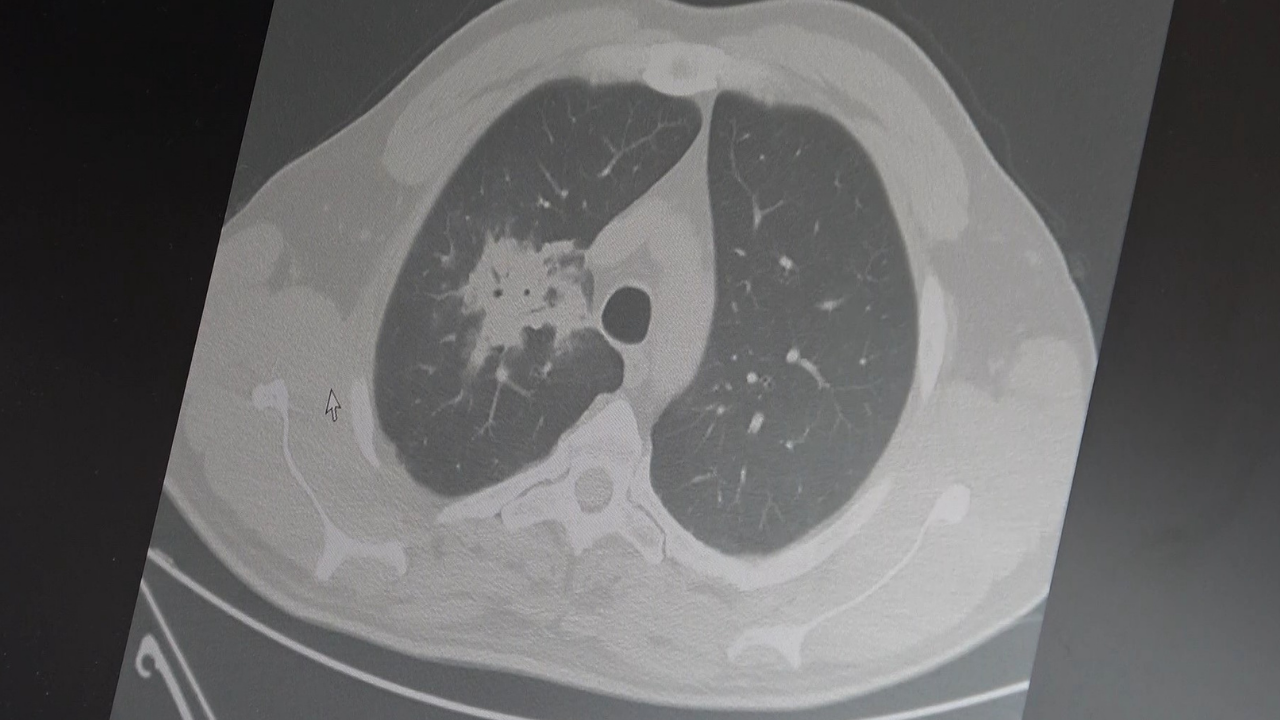

2024 yılında yayımlanan bir araştırmaya da değinen Özkaya, hem sigara hem elektronik sigara kullanan bireylerde akciğer kanseri riskinin, yalnızca sigara içenlere göre yaklaşık dört kat daha fazla olduğunun tespit edildiğini aktardı.